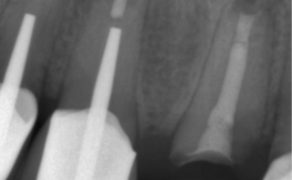

Streszczenie: Kanały o dużym stopniu zakrzywienia stanowią dla lekarza stomatologa szczególne wyzwanie, gdyż taka morfologia zwiększa prawdopodobieństwo wystąpienia powikłań. W artykule przedstawiono opis przypadku leczenia kanałowego zęba z zakrzywionymi kanałami. Omówiono klasyfikację zakrzywionych kanałów korzeniowych, jak również metody leczenia zębów ze znaczną krzywizną kanałów, najczęściej występujące powikłania oraz sposoby zapobiegania im.

Summary: Severely curved root canals are a challenge for a dentist since such a morphology increases the probability of complications during treatment. The article describes a case of root canal treatment of a tooth with curved canals. The classification of curved root canals is discussed as well as methods of treating teeth with severe root canal curvature, the most common complications and ways of their prevention.

Chemo-mechaniczne opracowanie systemu kanałowego jest etapem leczenia kanałowego, którego celami są usunięcie zmienionej chorobowo miazgi, eliminacja mikroorganizmów oraz takie ukształtowanie kanału [...]